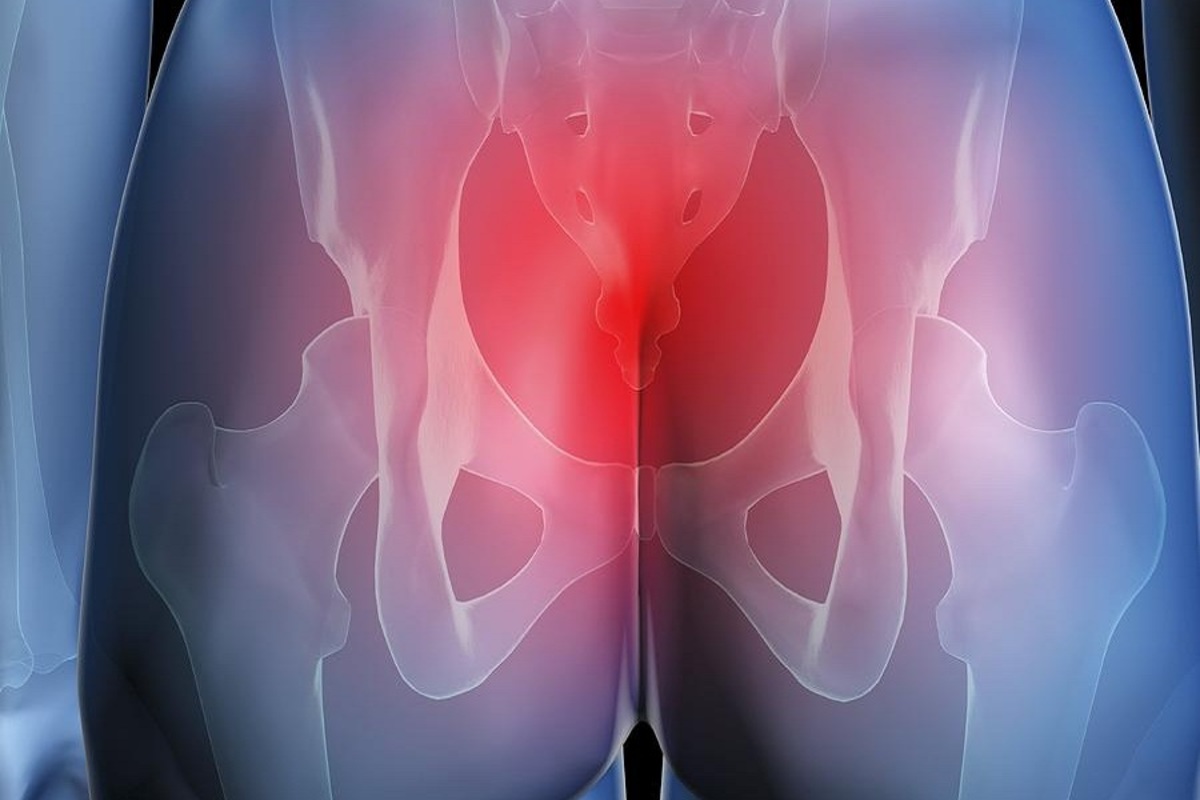

Боль в малом тазу у женщин: Причины и подходы к лечению